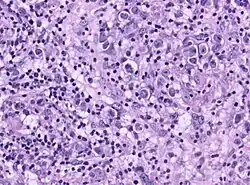

Гистология

Опухоль однородна по внешнему виду, состоит из двух видов клеток: крупных клеток (являются истинными опухолевыми) с везикулярными ядрами и прозрачной или мелкозернистой цитоплазмой, которая является эозинофильной. Мелкие клетки, располагающиеся в кластерах или хаотично смешаны с опухолевыми клетками[2]. Микроскопическое исследование выявляет однородные клетки, которые напоминают первичные зародышевые клетки. Как правило, строма содержит лимфоциты, и около 20 % пациентов имеют саркоидоподобные гранулемы. Иммуногистохимический метод исследования определяет, что более 70 % лимфоцитов представлены Т-лимфоцитами, остальное приходится на В-лимфоциты.

Герминомы, содержащие гигантские синцитиотрофобластные клетки были отнесены в отдельную группу (К. Sano)[3].